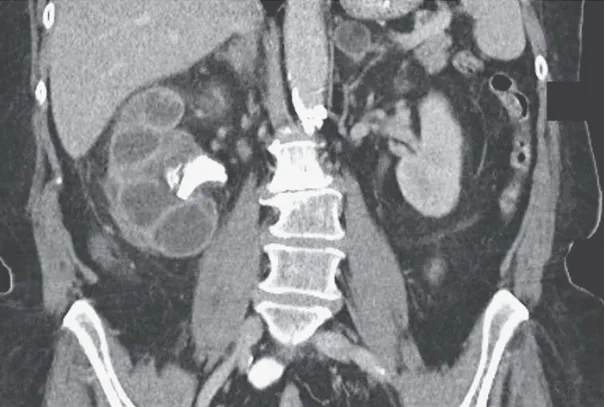

IRA + Icterícia: Um Caso que Exige Investigação Detalhada